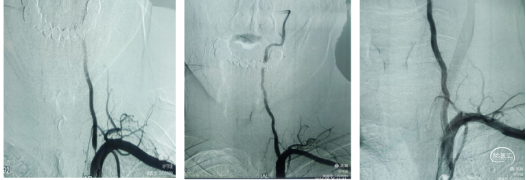

回撤5F中间导管于颈总动脉造影显示颈内动脉起始段重度狭窄。(下图1)

在C1段置入5mm保护伞,用3mm和4mm球囊扩张狭窄部位,但撤出球囊后狭窄略有改善。(下图2)

置入6~8~40mm自膨支架,支架位置良好,残余狭窄约30%。(下图3)

回撤导管与颈总动脉造影支架位置良好,远端大脑中动脉显影良好,分叉部无明确血栓征象。可能经替罗非班推注和血管通畅后逃逸的小血栓溶解了。再通后流动的血液就是最好的溶栓剂。